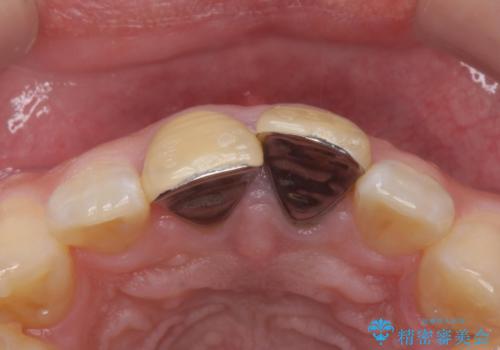

- 前歯のかぶせ物の変色を主訴に来院された患者様です。

根管治療からのやり直しはご希望されませんでした。

今回はe-maxクラウンで修復していきます。